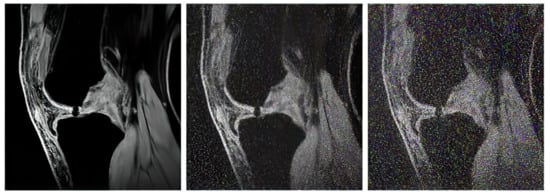

In our study, we use three variable sequences of articular cartilage, including T2-weighted images, proton density-weighted images, and gradient echo images. For each mentioned group, we tested in total of 1000 MR images from the public database Osteoarthritis Initiative (OAI) [71,72] to provide a robust comparison among individual segmentation approaches.

The proton density-weighted MR imaging is able to recognize in contrast the cartilage defects and abnormal cartilage composition in their tissues. This imaging sequence enables a suitable investigation of the cartilage morphology, ligaments, and menisci. The fat-saturated proton density-weighted images are suitable for the investigation of a low-signal intensities, which is a typical case of early cartilage loss. Therefore, this technique is well suited for the examination of osteoarthritis. As an example of the articular cartilage data, we provide a comparison of various sequences from the same cartilage area (Figure 4).

Proton density sequence plays an indispensable role in structural investigation of the early stage of articular cartilage loss. Here, only a weak contrast between a common cartilage surface and such pathological findings are notable. Therefore, for our analysis these data are substantially important. To objectivize such findings, we provide the example (Figure 5) from our dataset, where such investigations can be observed.